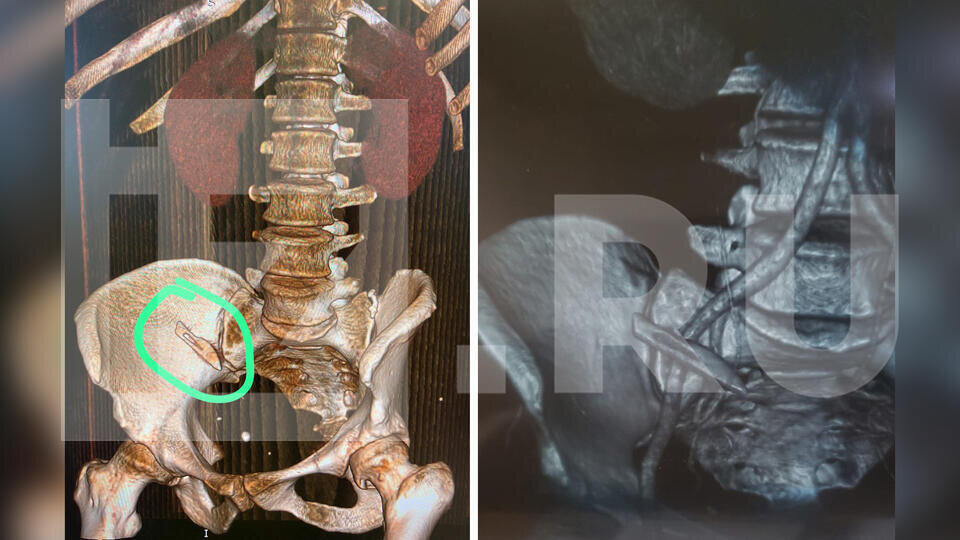

Больше двух месяцев Яна об этом даже не подозревала – ходила на работу, летала в Екатеринбург на химиотерапию. Там и обнаружили ошибку сочинских врачей. Во время компьютерной томографии медики увидели лезвие. Скальпель был вплотную прижат к главной артерии организма, любое неловкое движение могло привести к смерти.

Фото: © скриншот видео